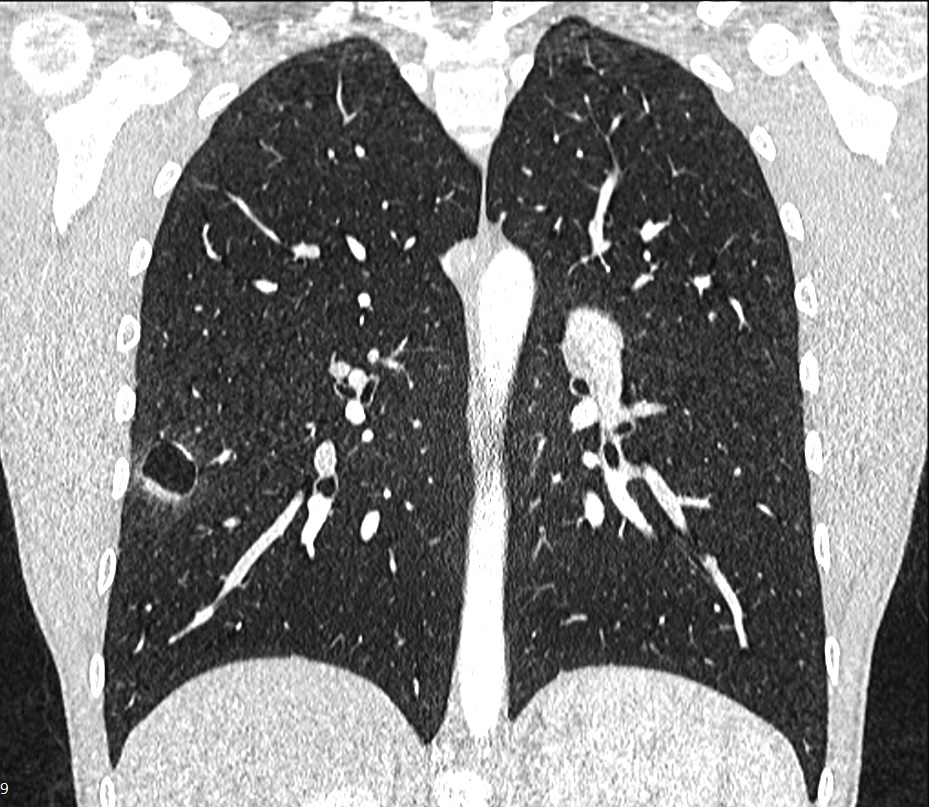

Figure 1. Chest CT scan.

Inflammatory myofibroblastic tumors (IMT) are relatively benign tumors that can occur in the lung, and also arise from different anatomical locations. In the lung, an IMT can be a solitary pulmonary nodule or a locally invasive lesion. The authors share the case of a 15-year-old male patient who presented with occasional hemoptysis. A chest computed tomography (CT) scan showed a cavitary lesion in the right lower lung lobe. A thoracoscopic segmental resection was performed, and the pathological result was an IMT. To the best of the authors’ knowledge, there are very limited reports of a lung IMT presenting as a cavitary lesion in the English literature.

Figure 2. Cavitary lesion in the right basomedial segment.

The authors report on the case of a 15-year-old male patient who presented with a two-year history of recurrent hemoptysis (about 60 ml), occurring once every three to four weeks. The hemoptysis was not related to physical activity or other respiratory symptoms and was self-limiting. The patient underwent a diagnostic fiber optic bronchoscopy that was inconclusive. A chest CT scan showed a cavitary lesion in the right basomedial segment of the right lower lobe of the lung. The patient's case was discussed in a multidisciplinary board meeting, and it was agreed that the right lower lobe lung lesion was the most probable cause of the patient's condition. The team planned a thoracoscopic uniportal video-assisted segmental resection of the right basomedial segment of the right lower lobe. The operative course was uneventful. The chest tube was removed three hours after the surgery, and the patient was discharged home on postoperative day one.